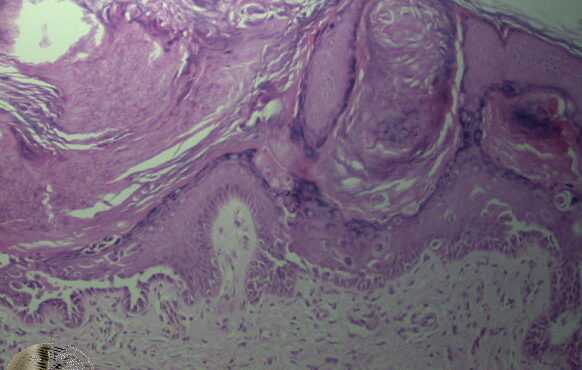

Darier =داء داريير Dariers Disease Darier’s disease is usually transmitted in an autosomal dominant pattern. It has been found to be due to mutations in the ATP2A2 gene on chromosome T2, which encodes the sarcoplasmic/endoplasmic reticulum calcium pumping ATPase SERCA2 (206). The gene is 12q23-24.1. In typical cases, there is a more or less […]